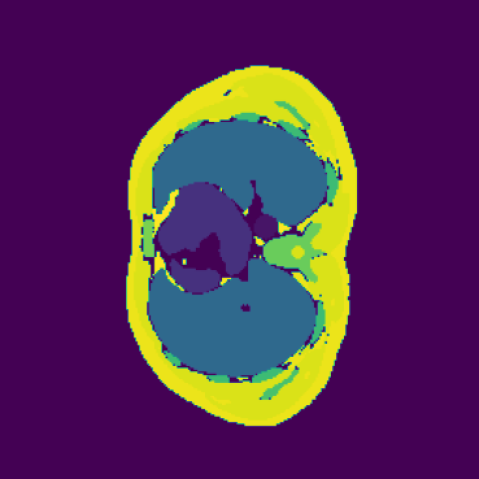

As shown in Figure 5, the generated slices exhibit high consistency across adjacent slices. The anatomical structures and semantic patterns are smoothly and coherently preserved between slices, indicating that our model is capable of generating 3D-consistent synthetic images rather than isolated 2D slices.

In our approach, we employ a compression factor of 4 to encode 3D medical images into the latent space. This level of compression reduces the spatial resolution of the original image (e.g., from 256×256 to 64×64 per slice), while still preserving the essential anatomical structures and semantic content. The latent representation at this scale offers a favorable trade-off between dimensionality reduction and semantic fidelity. Specifically, although fine-grained textures are simplified, key structural patterns (e.g., organ boundaries, lesion shapes) remain visually distinguishable and semantically coherent. As the compression rate increases, the latent representations become progressively more abstract. With lower compression (e.g., 2× or 4×), the latent features preserve key anatomical structures and spatial layouts, making them beneficial for our semantic image synthesis task in latent space, as the model can operate on compressed representations that retain sufficient semantic information without being overwhelmed by high-frequency noise. In contrast, higher compression rates (e.g., 8× or above) lead to a loss of fine-grained details and reduced semantic fidelity. The choice of a 4× compression thus ensures that the latent features are compact and meaningful, facilitating effective conditional generation while significantly reducing computational overhead. We therefore adopt a 4× compression as a compromise between computational efficiency and semantic preservation. The corresponding 2D slices in image space and latent space are shown in Figure 7.